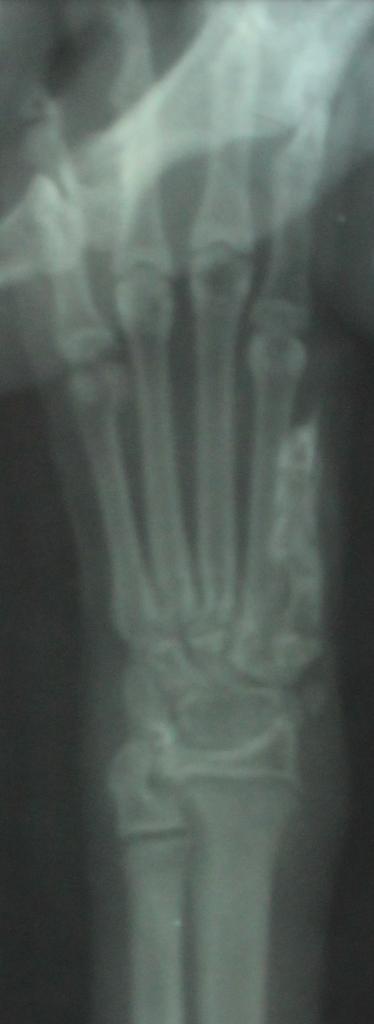

По умолчанию рентген передней лапки котёнка

ID:	3353072 и никаких раздробленных костей не видно, как утверждал врач из Амулета.

О том, что перелома не было и нет, подтвердил и сам ветеринар, к которому я успела заехать после рентгена сегодня вечером.

вот и не лень вам писать всякую чушь... специально увеличила снимок, чтоб лучше было видно... специалистам (если тут они вообще есть), а ни тем, кому что-то кааажется... SHADOW (она же ТЕНЬ), вам в другую тему... https://forumodua.com/showthread.php?t=5412

Вот не задача не продумала такой пустяк... лапка у котенка на снимке то левая, а повреждена то правая...! Хотя тем кто не видел котенка можно же лапшу на уши намотать... да?

Снимки с каким то разным оттенком один черно-белый и четкий а второй мутновато-непонятного цвета.

Просто очень давно у меня палец большой на руке после травмы гнил, загноилась кость в общем история длинная, но одно могу сказать за 6 месяцев что у меня эпопея с пальцем была мне тонну снимков сделали, поэтому на снимки я насмотрелась достаточно. Эти 2 снимка были сделаны на разных рентген аппаратах, это я могу сказать с полной уверенностью!

То что лапа на снимке взрослого кота, а не 3-4 месячного котенка тут я полностью согласна, то что котенок был это факт 100% сама лично видела в клинике, если надо то вспомню дату. С масиком все будет в порядке, ему вовремя помощь оказали